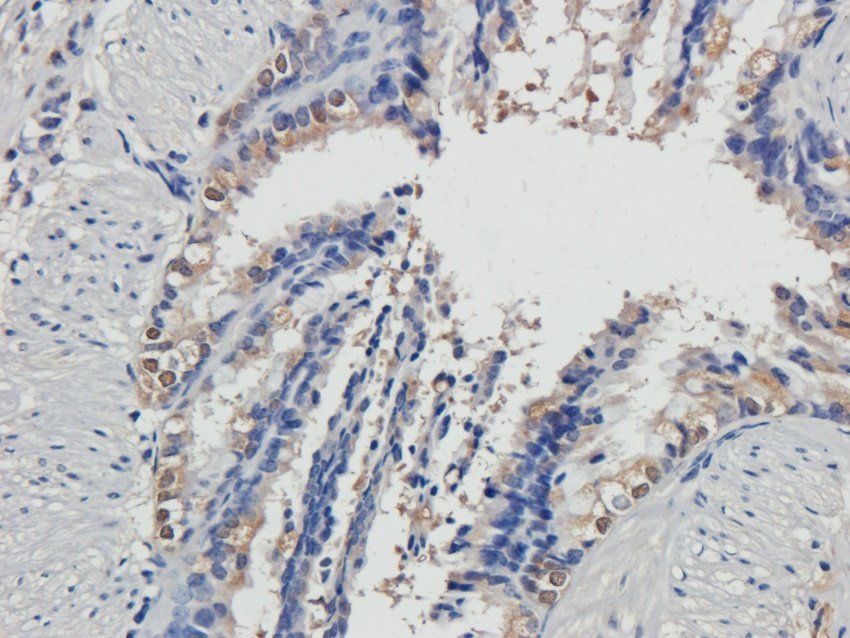

应用稀释比例:WB: 1:200-2000, IHC-P: 1:100-500, IF/ICC: 1:100-500

文献和实验3) 依赖性细胞死亡来介导中暑。 热应激通过热休克转录因子 1 (HSF1) 增加 ZBP1 的表达,并通过独立于核酸感应作用的机制激活 ZBP1。ZBP1、RIPK3 或混合谱系激酶域样 (MLKL) 和 caspase-8 的缺失降低了热应激诱导的循环衰竭、器官损伤和致死率。因此,ZBP1 似乎具有协调宿主对热应激反应的第二个功能。 临床上,中暑的特征是极度高热、全身炎症反应、循环衰竭、出血和凝血障碍,以及热相关细胞毒性、炎症和弥散性血管内凝血 (DIC) 之间复杂相互作用导致的多器官

,4046 个蛋白质被定量。与对照组相比,CUMS 组在 1.5 倍变化 (> 1.50 或 差异蛋白验证:免疫荧光证实,与对照组相比,海马 CA1 和 DG 亚区的神经元损失显著。对 RIP3、MLKL 和 p-MLKL 及与铁稳态失调和脂质过氧化相关指标,包括 Ftl1、MDA、GSH 和 GPX4 等进行 WB 验证,结果表明铁死亡和坏死与慢性应激诱导的抑郁有关。 6.2、IF 3-5 分文章:蛋白质组学+代谢组学 蛋白质组学和代谢组学检测 分析差异蛋白,对差异蛋白进行